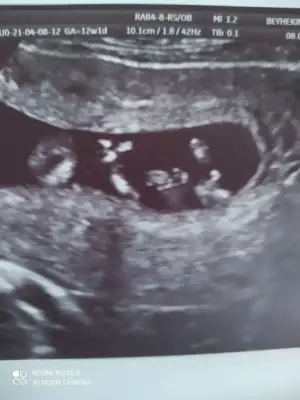

dr soylemeden siz gorun genital nub teorisi ( bebegin cinsiyeti)

Ikra meyra Ikra meyra canim 12+2 bı tahmin de bulunurmusun.İlk bebeğimi bilmistin ya.bunada yorum yaparsan sevinirim.tesekkurler .

• IMG_20210408_180426.webp

IMG_20210408_180426.webp

29 KB · Görüntüleme: 79